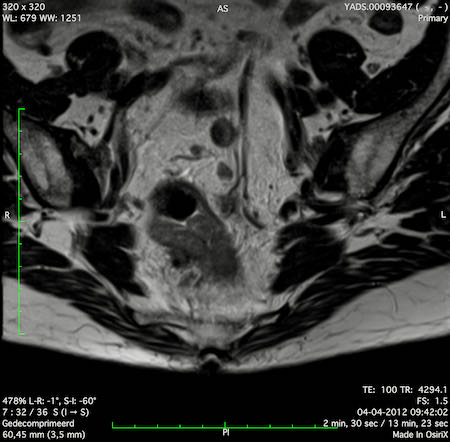

Hình ảnh

Các hình ảnh được cung cấp cho thấy ung thư biểu mô tế bào nhẫn với tình trạng dày lan tỏa thành trực tràng, hình ảnh bia bắn điển hình, và sự xâm lấn mỡ mạc treo trực tràng.